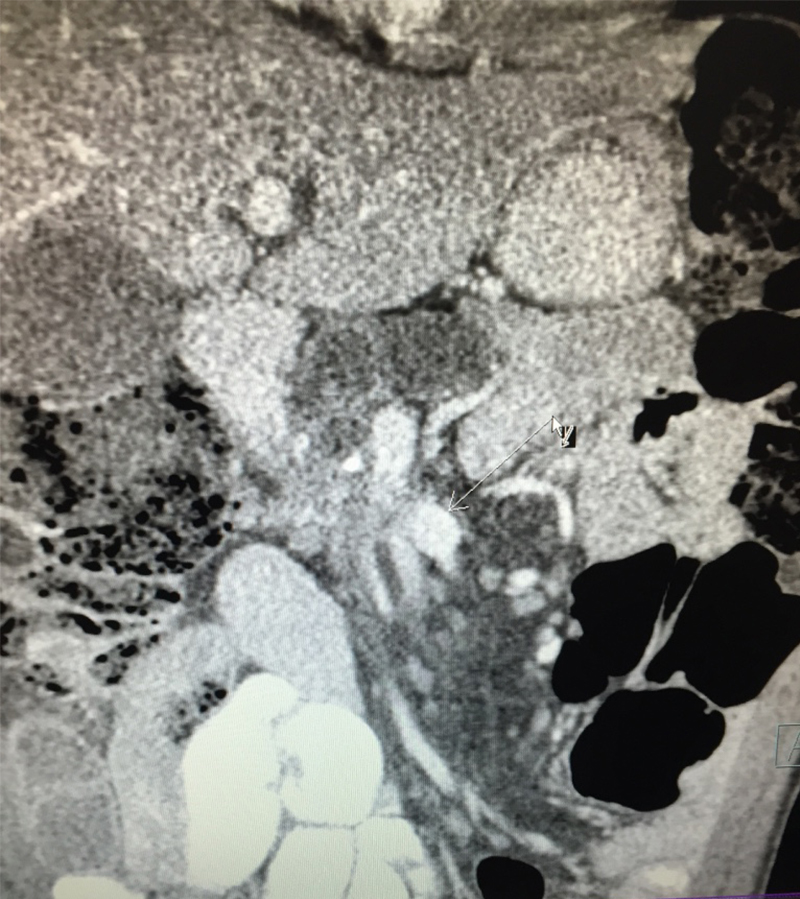

A 54 year old gentleman with long history of alcohol dependence & background of chronic pancreatitis, came with loss of appetite, loss of weight, back / abdominal pain, jaundice and loose motions. On thorough investigations CA 19-9, a tumor marker for pancreatic cancer and bilirubin were significantly elevated. A pancreas protocol computed tomography (CT) of the abdomen revealed a tumor in the head of pancreas in the chronic pancreatitis background. It was compressing / narrowing important gut vein (superior mesenteric vein - SMV). The pancreatic duct and the common bile duct were both dilated due to obstruction. Based on history, tumor markers and CT findings, provisional diagnosis was pancreatic ductal adenocarcinoma (PDAC) with involvement of SMV. There was no sign of any distant metastasis on PET-CT scan. Patient underwent endoscopic ultrasound (EUS) for a biopsy sample. The biopsy confirmed the cancer. A Whiple pancreatoduodenectomy procedure involving removal of cancer bearing portion of pancreas along with part of stomach, bile duct and entire duodenum was removed. Draining lymph nodes were removed. The involved portion of SMV was resected along with pancreas and the vein was reconstructed, a step done in exceptional cases and only by experienced surgeons. Patient recovered uneventfully and was later administered adjuvant chemotherapy. To know more about pancreatic cancer click here

• This is a borderline resectable pancreatic cancer (where the important gut vein SMV is partially or completely involved

• Involvement of SMV is not a contraindication for surgery, as long as it is possible to reconstruct the involved vein